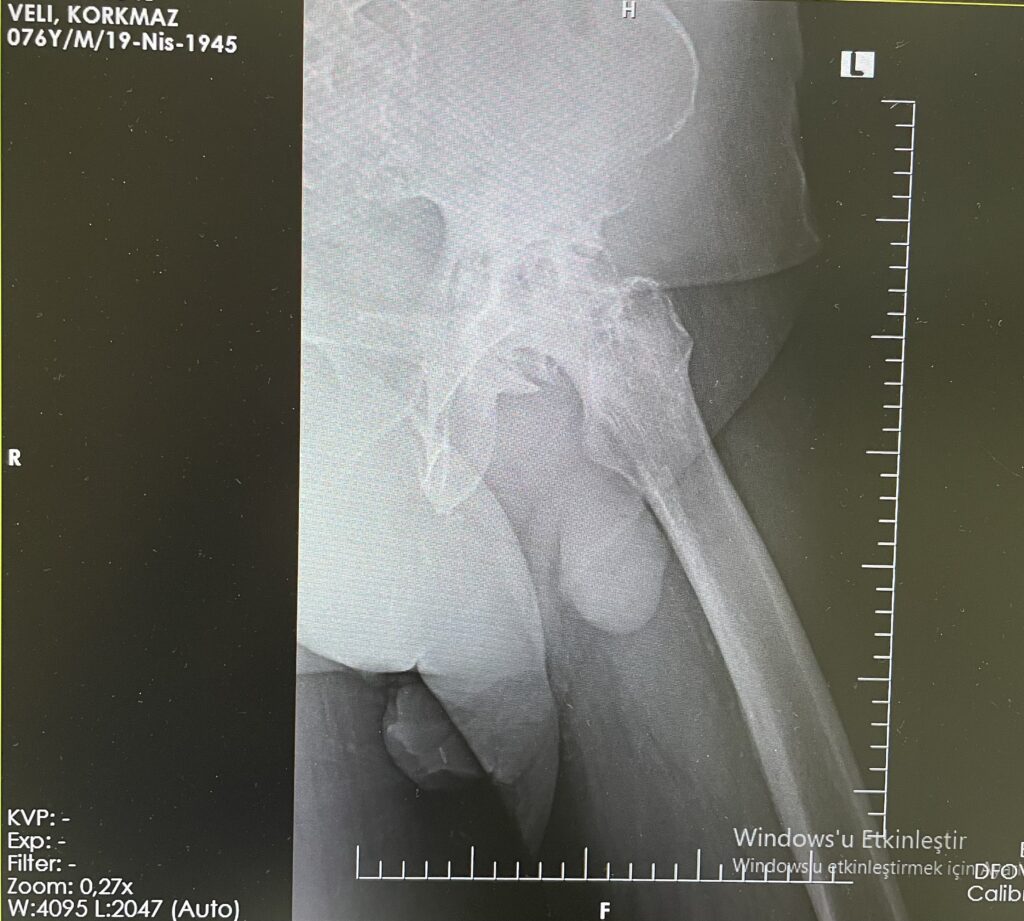

V.K.